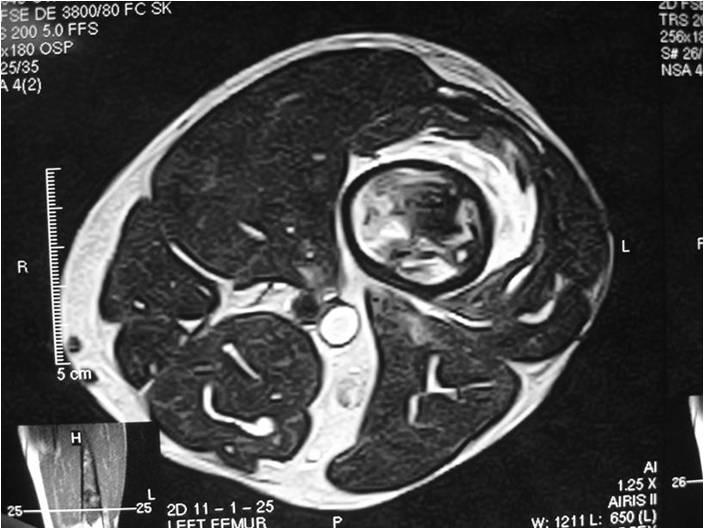

Radiology emulates pathology: Biphasic Tumor

- One region low grade chondrosarcoma

- Second more aggressive area with bone destruction, lysis of calcification, soft tissue mass

- Cortical permeation and a soft tissue mass in 70% of cases

Ill-defined, lytic intraosseous lesion

- Or extraosseous soft tissue mass

- Devoid of calcifications in continuity with lesions having the features of a cartilaginous tumor

Characteristically abrupt transition between chondroid tumor and dedifferentiated, lytic component

(Right Arrow)Aggressive Lytic Area (Dedifferentiated Sarcomatous Component) Cortical Destruction Soft Tissue Mass without Calcification